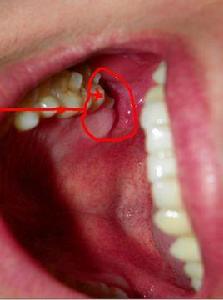

立事牙就是智齒。 它位於牙列後部,由於現代人口腔功能退化,智齒都是很晚萌出。 而且很大一部分都是阻生。阻生的意思就是他頂著前邊的牙。別的牙都朝上長, 他卻橫著長。 阻生會有很多影響。 例如臨床上最常見到的 智齒冠周炎。